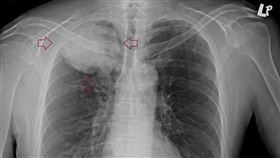

頭暈就醫竟肺癌末期 只剩3個月可活

50多歲的男性患者、偶爾咳嗽一個多月,最近感到頭暈雙...